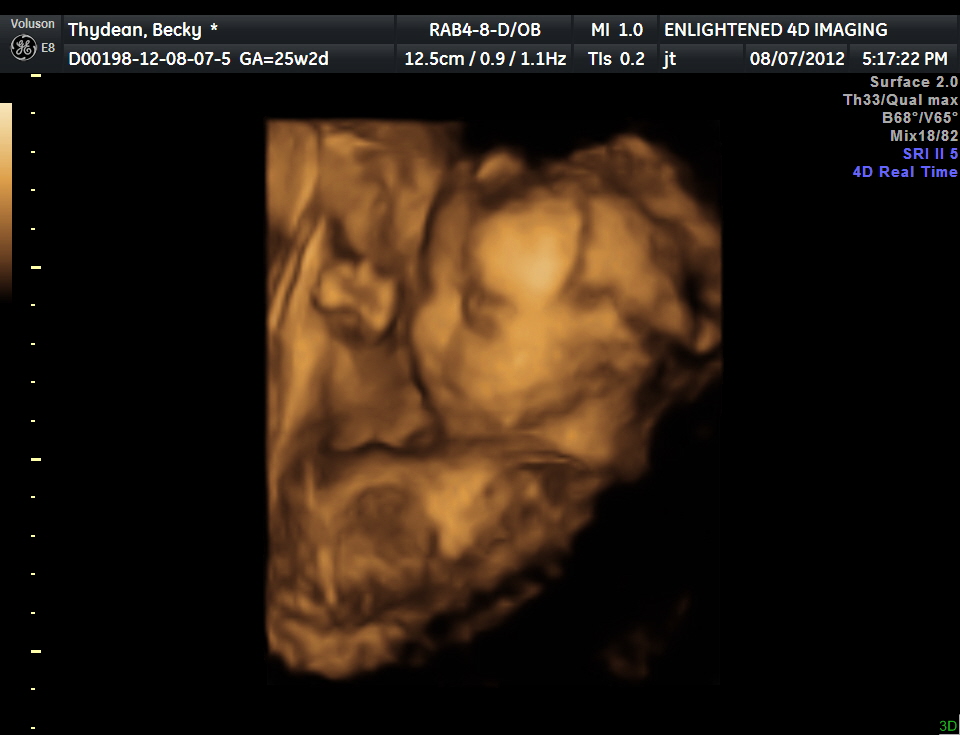

3d 4d Ultrasound Illinois Normal Champaign Lincoln